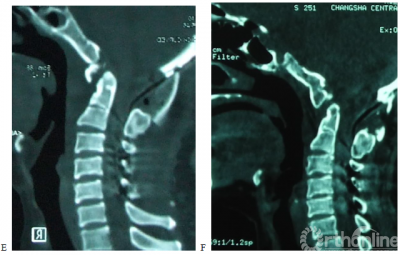

图1. 女,50岁,合并颈2/3分节不全,类风湿关节炎病史13年。A,术前X片示齿突向头侧移位,突入枕骨大孔内;B,术前CT示寰枢关节间异常骨性连接,齿突向上移位,超过McRae线7.02mm;C,术前T2加权MRI示上颈髓受压,CMA为109度; D,E术后X片及CT示齿突复位,低于McRae线9.89mm;F,G术后3年CT及三维重建示齿突复位得到维持,枕颈牢固融合;H,术后3年T1加权MRI示上颈髓受压解除,CMA改善到到155度。